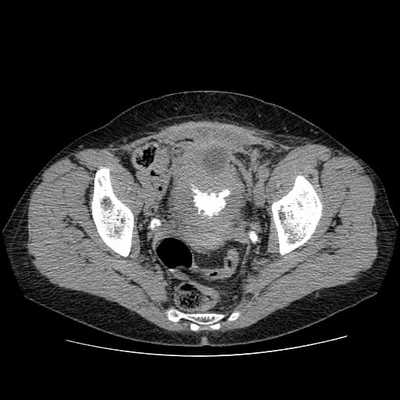

Что покажет МСКТ мочевого пузыря

КТ мочевого пузыря и почек хорошо показывает размер органов, их форму, расположение и соответствие нормам. Такая диагностика назначается при подозрении на:

Список основных симптомов и показаний для проведения МСКТ мочевого пузыря включает появление у пациента острой или тупой боли неясного характера в нижней части живота, задержку, затрудненное либо слишком частое мочеиспускание. Также эта форма диагностики используется как метод дообследования пациентов с неясными результатами УЗИ, когда есть подозрение на опухолевый процесс и нужно уточнить его локацию, характер и злокачественный потенциал.

КТ мочевого пузыря

КТ мочевого пузыря - надежный и точный метод исследования, применяемый в дифференциальной диагностике заболеваний органов малого таза. Компьютерная томография основана на применении рентгеновских лучей и способности тканей человеческого тела поглощать их с разной интенсивностью. В процессе сканирования врач получает серию послойных изображений просвечиваемой области, что позволяет диагностировать малейшие патологические изменения мочеполовой системы.

Что покажет КТ мочевого пузыря

В процессе компьютерной томографии врач получает возможность оценить форму, размер и границы обследуемого органа, выделить особенности структуры и патологические изменения строения. Сканирование мочеполовой системы с помощью томографа выявляет следующие заболевания:

наличие камней в просвете мочеточника, почечной лоханке и полости мочевого пузыря;

патологическое расширение или, наоборот, стеноз мочеточников;

воспалительные изменения стенок мочевого пузыря и окружающих тканей;

эрозии, язвы слизистой оболочки мочевого пузыря;

новообразования в области органов мочеполовой системы;

травматические поражения стенок органа.

КТ мочевого пузыря, усиленное контрастированием, визуализирует кровоснабжение рассматриваемой области, состояние кровеносных сосудов и лимфатической системы. В результате получения тонких срезов изучаемых тканей врач фиксирует малейшие изменения в них и выявляет заболевания на ранних сроках.